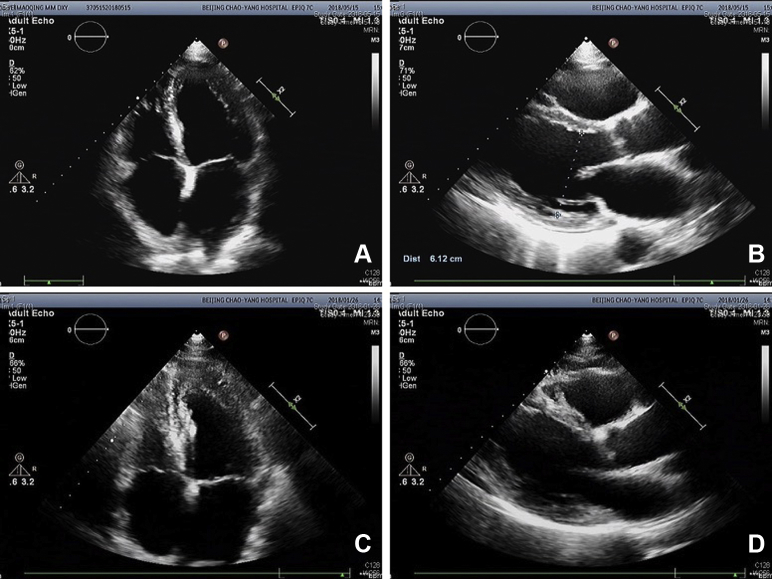

Upon the patient’s presentation to our hospital, blood test results showed an abnormal elevation in B-type natriuretic peptide levels, with a value of 1186 pg/mL (0–100 pg/mL). Compared with the patient’s ultrasound cardiography (UCG) 4 months prior, his recent UCG showed marked enlargement of the heart, with a left ventricular end-diastolic diameter of 61 mm, a right ventricular internal diameter of 43 mm, and reduced ejection fraction of 41% (Figure 1). The patient had extremely elevated levels of serum ferritin, with a value of 2497.80 ng/mL. Magnetic resonance imaging showed a significant decrease in signal intensity on T2-weighted images in the liver parenchyma (Figure 2). The ECG obtained on initial presentation revealed a J-point elevation of >2 mm, followed by T-wave inversion in the right precordial leads (V1 to V3) (Figure 3A). On the third day after admission, the patient started feeling severe dyspnea associated with intermittent palpitations. Urgent ECGs were performed and evaluated (Figure 3B), which showed frequent regular, wide QRS complex tachycardia with a rate of 100 beats per minute.

Figure 2.

Abdominal magnetic resonance imaging.

The patient experienced progressive dyspnea with edema in both lower extremities. B-type natriuretic peptide levels were abnormally high and UCG showed that the whole heart was significantly enlarged, which confirmed that the patient had developed cardiomyopathy and congestive heart failure. Because this patient had received a large volume of RBCs to relieve his severe myelosuppression symptoms, he had extremely elevated levels of serum ferritin, with a value of 2497.80 ng/mL. Serum ferritin can reliably predict cardiac iron overload when levels are >2485 ng/mL.2 The manifestation of his abdominal magnetic resonance imaging, a significant decrease in signal intensity on T2-weighted images in the liver parenchyma, is consistent with iron overload. Cardiac iron deposition can result in cardiomyopathy, arrhythmia, and heart failure.3 We suspected that cardiac iron overload was the underlying cause of the patient’s ECG abnormalities and clinical manifestations. In addition, the management of heart failure and iron chelation therapy led to resolution of VT and Brugada pattern, which also supported our suspicions.